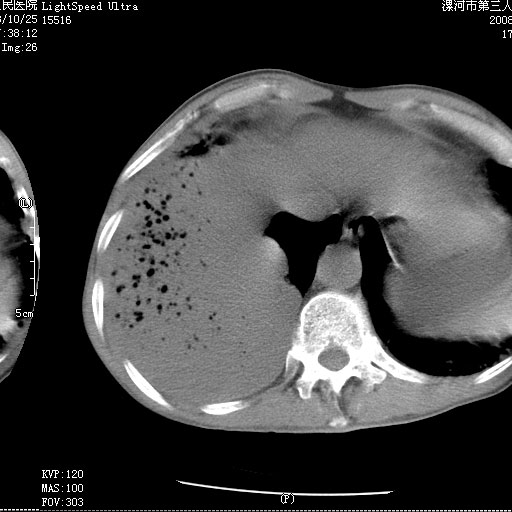

m 老年 发烧、呼吸困难,慢支、肺气肿多年;记的那次是下午大概17:38做的,晚上窒息死亡。

上面的层面就慢性支气管炎肺气肿、肺大泡,别的没有什么、也就不传了。

当时我怀疑:1、阻塞性肺不张早期 2、肺脓肿早期,望老师们发表意见

应该是脓胸的表现,右下肺气管阻塞考虑为痰栓.

你怀疑的有道理,慢支、肺气肿、肺打泡是有了,右下肺的病变有待商议;

首先考虑右下肺炎症并不张,不除外早期肺泡癌改变

病灶边缘清---多个含气小腔---近端未见通畅气管影-----支持-----慢性肺脓肿继发阻塞性肺不张

阻塞性肺不张原因-----脓液未排出

1、右侧脓胸;2、copd;

3、细支气管肺泡癌可以排除,病变以斜裂为界,呈大片状高密度影,内可见多发小气泡,表明有产气杆菌感染所致,内无明显的支气管“枯树枝征”表现,再结合其临床改变(细支气管肺泡癌临表表现重、影像表现轻)所以不符合细支气管肺泡癌(炎症型)的改变。

考虑为右肺下叶支气管痰栓形成并阻塞性肺不张及肺炎。

病变按肺叶分布,病变内可见多个小空腔影,未见充气支气管影,中间段支气管管腔肺窗示密度欠均匀,下肺支气管分叉处基底段支气管隐约可见,未见明显狭窄,中叶支气管通畅,

考虑:阻塞性肺炎伴小脓肿形成可能性大。(痰栓可能性大)

右下肺实变,内有弥漫分面小气泡而无支气管征,叶间裂前移,呈臌大之形,而无收缩之状,兼纵隔稍左行移,故。不支持不张,倒支持大叶肺叶,如楼上所说,小气泡不象残留之肺,不可以考虑产气菌感染吗。

阻塞性肺炎,肺脓肿形成。依据,右下支气管不通,大片实变形内可见小气泡。不支持肺不张。